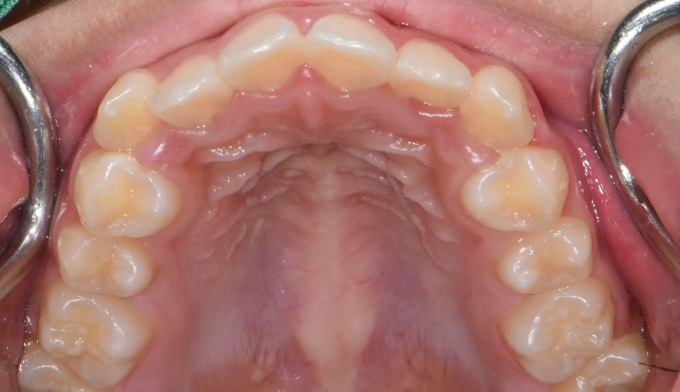

덧니

심하지 않은 덧니의 경우에는 교정기간이 비교적 짧습니다.

확장장치와 같은 부가적인 교정장치가 필요없기 때문에 교정기간이 단축될 수 있습니다.

총 교정기간은 13개월입니다.